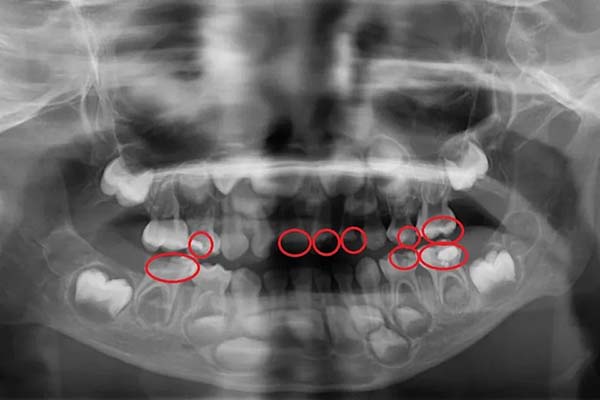

(图片 26cs05b)●X光看见孩子多颗蛀牙(红圈处均是蛀牙处)。